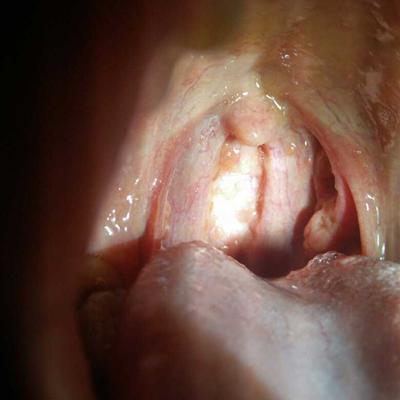

Esophagitis is esophagitis, which is caused by the stimulation or injury of esophageal mucosa, superficial or deep tissue, edema and hyperemia of esophageal mucosa. Chemical stimulation includes hygiene, bile, liquor, strong acid and strong alkali drugs. Physical stimulation includes hot food, drink, esophageal foreign body, etc. long term placement of nasogastric tube, etc. due to chemical treatment, esophagitis can be divided into three types, Radiation therapy can cause local damage to the esophagus, or reduce the patient's own resistance, leading to straw bacteria, fungi, or virus infection can also cause esophagitis, the most common in clinical is reflux esophagitis caused by gastric acid reflux. Now let's share with you.

Third: esophagitis, its main clinical manifestations are heartburn, swallowing pain, difficulty, and sternal pain. When esophagitis is serious, it can cause esophageal spasm and esophageal stricture, feel choking when swallowing food, and even vomit. Generally, esophagitis has less bleeding, but it can also cause hematemesis or melena, Esophagitis caused by different causes can be accompanied by corresponding clinical symptoms.